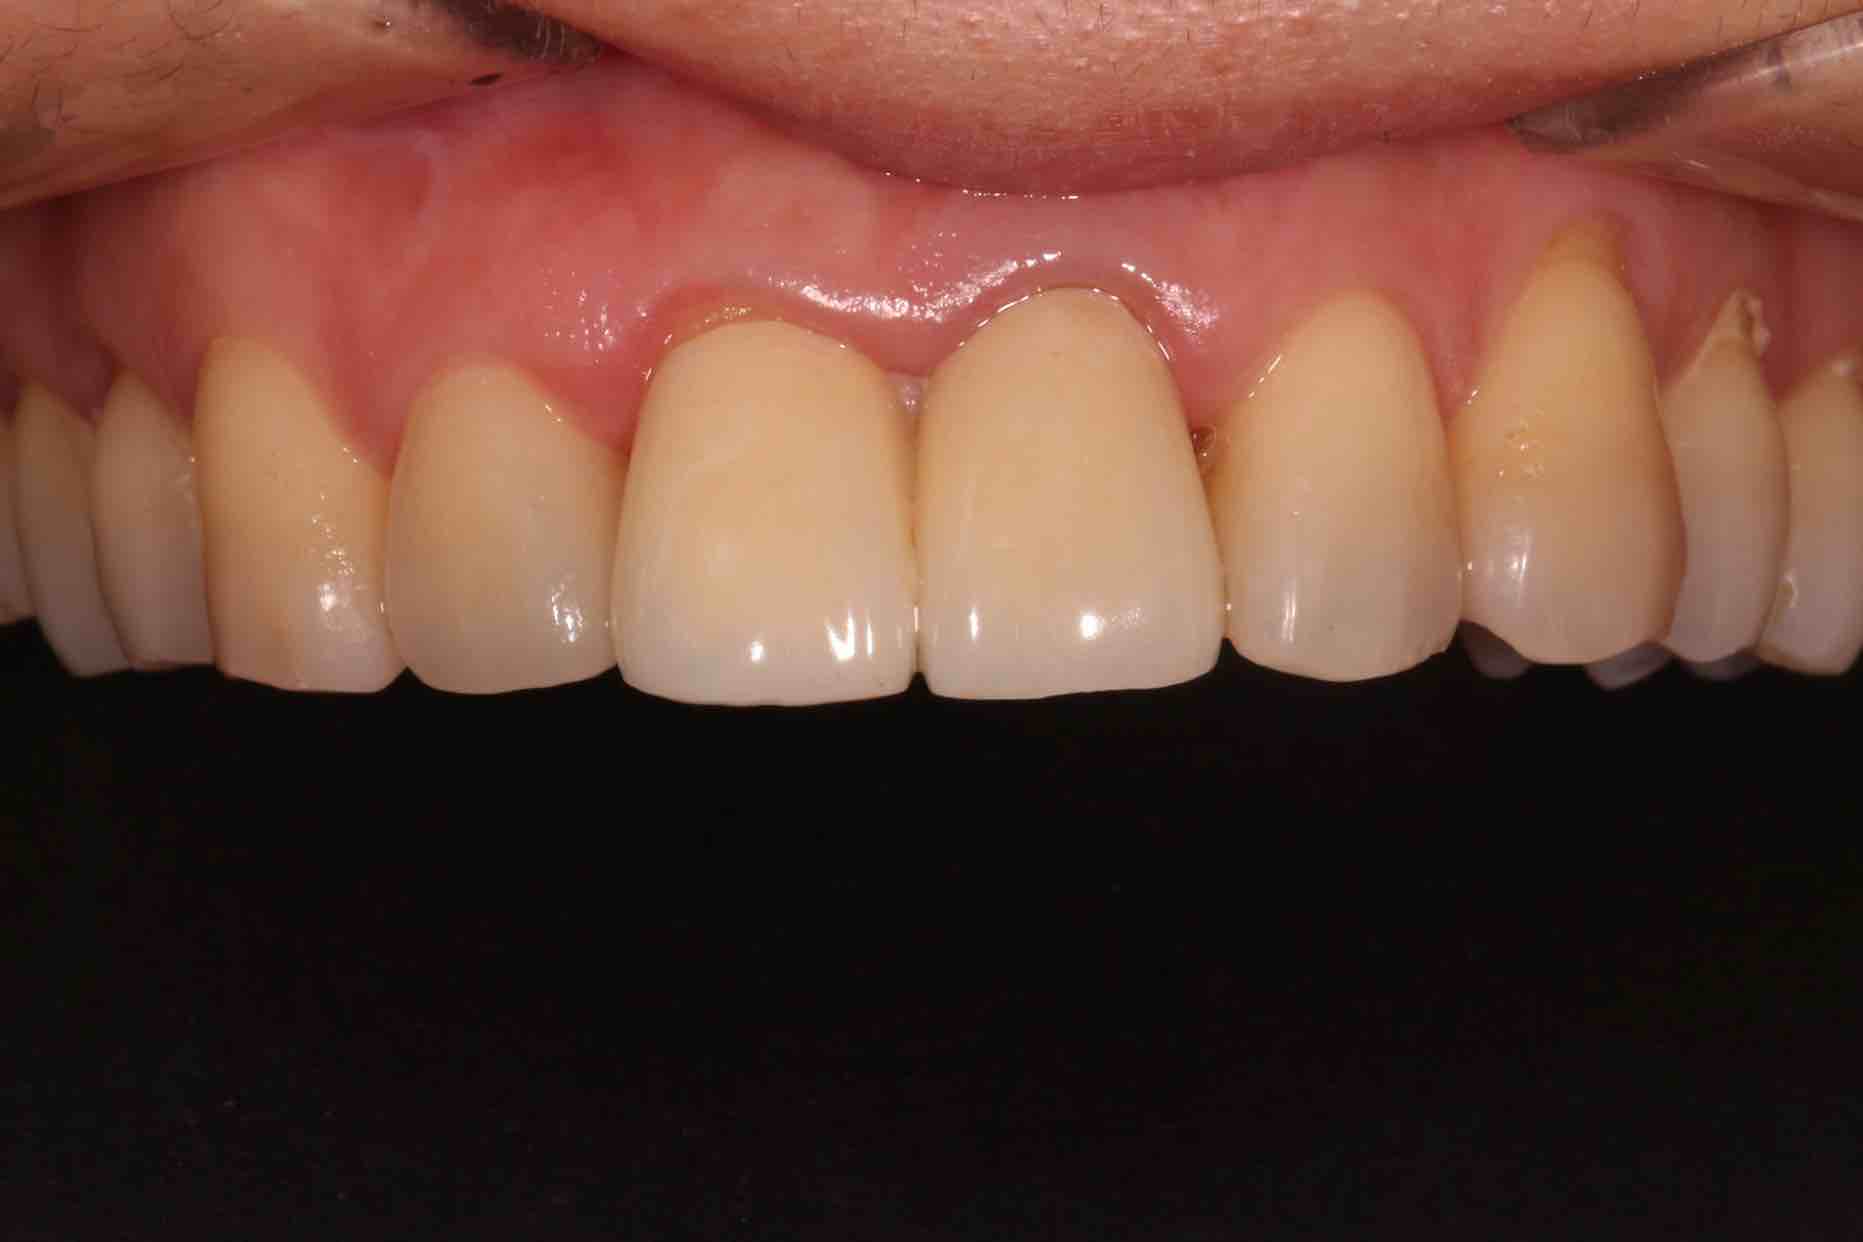

患者中年女性,11、21外院制作烤瓷冠,冠边缘不密合,牙龈退缩发黑,龈缘红肿,颜色不美观且X线检查21根管治疗不完善,由于牙冠不密合,11严重龋坏已有牙髓炎症状,我们对11进行了根管治疗,21进行了根管再治疗,最后CEREC扫描修复。